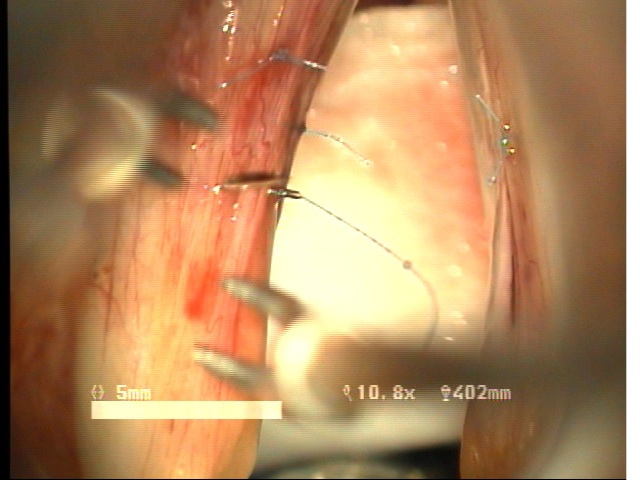

예송이비인후과 음성센터 김형태원장은 현재까지 난치성질환으로 특별한 치료방법이 없었던 "성대구증을 동반한 성대점막교(mucosal bridge of vocal fold)" 의 새로운 수술적 치료방법으로 "Sandwith mucosal flap surgery" 수술방법을 최초로 개발하여 시행한 치료결과를 얻어 예비보고로서 제82차 대한이비인후과학회 학술대외에 발표하였습니다. 이번에 발표한 새로운 수술방법은, 특별한 치료방법이 없었던 성대질환에 새로운 수술적치료방법을 제시한 것으로서 매우 높은 음성개선효과를 나타내는 것을 확인할 수 있었습니다.

제82차 대한이비인후과학회 학술대회는 2008년 4월 25일(금)-27일(토) 까지 서울 그랜드힐튼 호텔에서 열렸습니다. 이번에 발표한 연구논문은 기존의 난치성질환으로 특별히 치료방법이 없었던 "성대구증을 동반한 성대점막교"에 새로운 치료의 길을 제시한 것으로 목소리 개선에 뛰어난 장점과 효과를 입증할 수 있었습니다. 국내에서 최초로 난치성 음성질환자들의 치료에 사용된 수술방법의 수술후 치료결과에 대한 임상연구결과와 내용은 아래와 같습니다. ![]() ![]() ![]() ![]() -------------------------------------------------------------------------- * 동영상 ... more 제목 : New surgical technique for mucosal bridge of vocal fold : sandwich mucosal flap surgery 목적 : 성대 점막교( mucosal bridge)는 파열된 성대낭종이나 성대구증등에 의해 생긴 점막의 관통된 연결을 갖는 성대질환으로 수술적 치료 후 음성개선이 매우 어려운 성대질환이다. 성대 점막교는 단순절제시 음성개선이 어려운 질환으로서 특별한 수술적 치료방법이 없는 상태이다. 이에 음성보존을 위한 치료방법으로 sandwich mucosal flap을 이용한 새로운 술식을 보고하며, 이 술식의 치료결과와 음성학적 변화를 알아보고자 하였다. 방법 : 2005년 4월부터 2007년 4월까지 예송이비인후과에서 성대점막교로 진단되어 sandwich mucosal flap 술식으로 수술을 시행받은 6명의 환자를 대상으로 후향적인 분석을 시행하였다. 원인적인 요인과 동반질환으로는 파열된 표피양낭종 3례, 성대구증 2례, 폴립양성대1례였다. 조사대상은 남녀 각각 3례 였으며, 평균연령은 34.8세였다. 평균추적기간은 12.4개월이었다. 6례 모두 sandwich mucosal flap surgery를 시행하였으며 1례에서 PDL 성대수술을 추가로 시행하였다. 술후 2개월과 6개월에 음성분석검사와 후두스트로보스코피검사를 통해 객관적인 음성평가를 시행하였으며, 음성개선에 대한 주관적인 음성만족도를 측정하였다. 통계적 유의성은 Wilcoxon Signed Ranks Test로 검정하였다. 결과 : 음성개선에 대한 주관적인평가로서 수술전 Voice Handicap Index는 평균 20.9에 비해 16.4로 호전되었으며, 공기역학적검사상 성문하압은 감소되었으나 MPT은 오히려 감소되었다. 음성분석검사상 sPPQ, sAPQ, NHR, DSH는 모두 통계학적으로로 의미있게 감소하였다. 후두스트로보스코피검사상 6례 모두에서 성대점막파동의 의미있는 호전을 확인할 수 있었다. 합병증으로서 모든례에서 초기 애성이 두드러지게 나타났으며, 점막피판의 탈락이나 점막봉합사로 인한 이상은 초래되지 않았으며, 기침, 이물감 또는 객담과 같은 증상은 나타나지 않았다. 결론 : 성대점막교의 새로운 수술방법으로서 음성개선을 위해 시도된 sandwich mucosal flap surgery 가 매우 만족스러운 음성학적 치료결과를 나타내고 매우 유용한 술식이라 생각된다. |